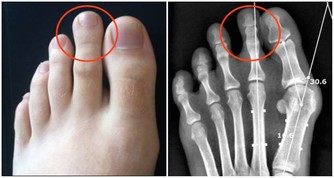

(5)內外八字

走路時,能走正的人其實很少,其中,內八字比較少見,多數人都是外八字。

外八字的成因與走路習慣有關,即移步時須左右移動重心,故而腳尖習慣向左右外撇。這樣的走姿,既不舒服也不雅觀。